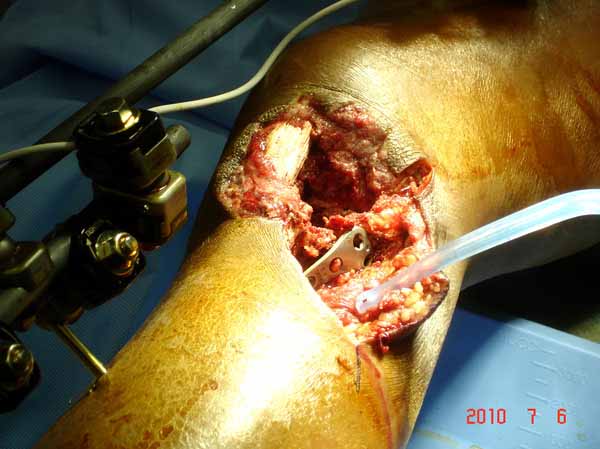

Клиника и течение заболевания похожи на однокамерную кисту. Больная молодая, желательно сохранить собственную головку. Надо спешить с операцией, иначе скоро произойдет перелом через тонкую стенку. Во время операции внутри будет пустота и небольшое количество жидкой крови.

Из всех перечисленных методов подходит вариант пластики аутокостью и усиление (арматура) шурупами. Основная задача сохранить интактную медиальную стенку и латеральный кортекс. Доступ передне-латеральный, но надо работать спереди шейки через небольшое окно в 10-15 мм. Фиксацию надо проводить между медиальной тонкой стенкой головки и латеральным кортексом. Каннюлированные шурупы 6.5 мм очень грубые и могут разрушить остаток стенки. Фиксировать надо кортикальными шурупами 3.5 мм, которые создадут мостик и арматуру в шейке. Провести по периметру шейки 4, и в центре пару шурупов. Во время операции и при манипуляции соблюдать осторожность, в любой момент может наступить стресс перелом. Заранее надо заказывать длинные шурупы!